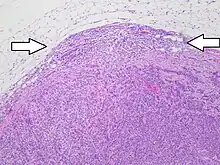

Histopathology of a lymph node with metastatic invasive ductal carcinoma from the breast, H&E stain, with the presence of extranodal (or "extracapsular") extension (arrows), as tumor outside the fibrous capsule of the lymph node.